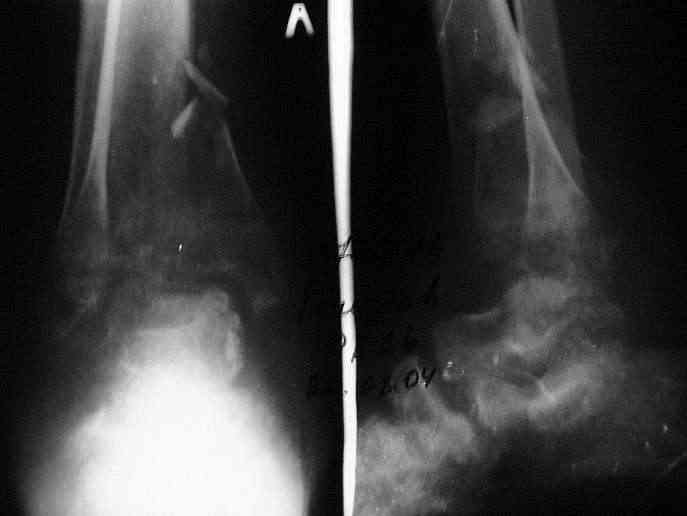

Здравствуйте, коллеги.Больной 26 лет, в 2004 году попал ко мне с диагнозом:синтезированный в аппарате Илизарова неполный внутрисуставной оскольчатый перелом дистального метафиза левой большеберцовой кости со смещением; выраженный остеопороз; множественное спицевое нагноение. Несостоятельность фиксации (костные отломки буквально "елозили" по спицам, несмотря наналичие упорных площадок).

Мной был демонтирован АВФ, удалены все спицы. Больной некоторое время лечился консервативно (шина Белера, антибиотики, перевязки). По заживлению и купировании гнойно-воспалительного процесса была произведена осткрытая репозиция, накостный остеосинтез 1/3 трубчатой пластиной.Такой вариант был принят из-за жуткого остеопороза и отказом больного от предложенного артродезирования голеностопного сустава сразу. Послеоперационный период без особенностей. Через год, больной пришел на осмотр на своих двоих, без дополнительной опоры, с жалобами на боли приходьбе в обл. г/стопа и с желанием замкнуть сустав. В операционной столкнулся с неожиданной проблемой по удалению пластины, она была глубоко вмурована в толщу склерозированного метафиза на глубину 1.5 см; удалить не рискнул (считал, что металл помешает в ходе реконструкции и требуется его удаление).

ЗЫ: Прошу прощения за очень низкое качество представленных ренгенограмм. Буду очень признателен за комментарии.